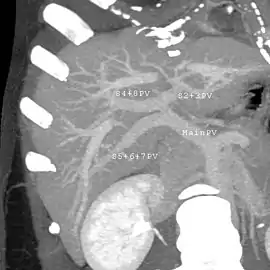

In the widely used Couinaud system, the functional lobes are further divided into a total of eight subsegments based on a transverse plane through the bifurcation of the main portal vein.[28] The caudate lobe is a separate structure that receives blood flow from both the right- and left-sided vascular branches.[29][30] The Couinaud classification divides the liver into eight functionally independent liver segments. Each segment has its own vascular inflow, outflow and biliary drainage. In the centre of each segment are branches of the portal vein, hepatic artery, and bile duct. In the periphery of each segment is vascular outflow through the hepatic veins.[31] The classification system uses the vascular supply in the liver to separate the functional units (numbered I to VIII) with unit 1, the caudate lobe, receiving its supply from both the right and the left branches of the portal vein. It contains one or more hepatic veins which drain directly into the inferior vena cava.[28] The remainder of the units (II to VIII) are numbered in a clockwise fashion:[31]